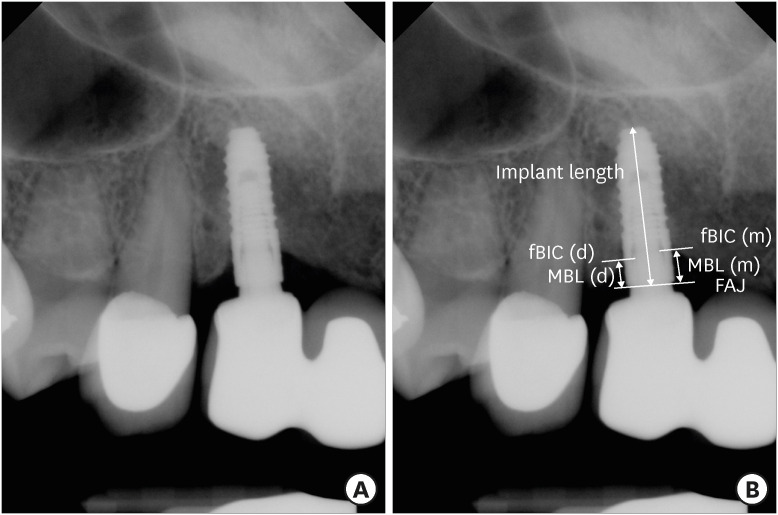

Methods: The study was conducted as a retrospective study involving 49 patients who had received 3.0-mm diameter TSIII implants (Osstem Implant Co.) at Seoul National University Dental Hospital. In total, 64 implants were included, and dental records and radiographic data were collected from 2017 to 2022. Kaplan-Meier survival curves and a Cox proportional hazard model were used to estimate the implant survival rate and to investigate the effects of age, sex, jaw, implant location, implant length, the stage of surgery, guided bone regeneration, type of implant placement, and the surgeon's proficiency (resident or professor) on implant survival. The MBL of the NDIs was measured, and the factors influencing MBL were evaluated.